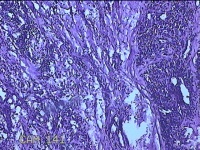

右侧手掌肉芽组织

性别

女

年龄

48岁

临床诊断

手掌开放性损伤

一般病史

右侧手掌肉芽组织增生

标本名称

大体所见

灰白暗红色带皮肤样组织1.3x0.8x0.3cm一块,切面灰白粉红色,质软。

图1